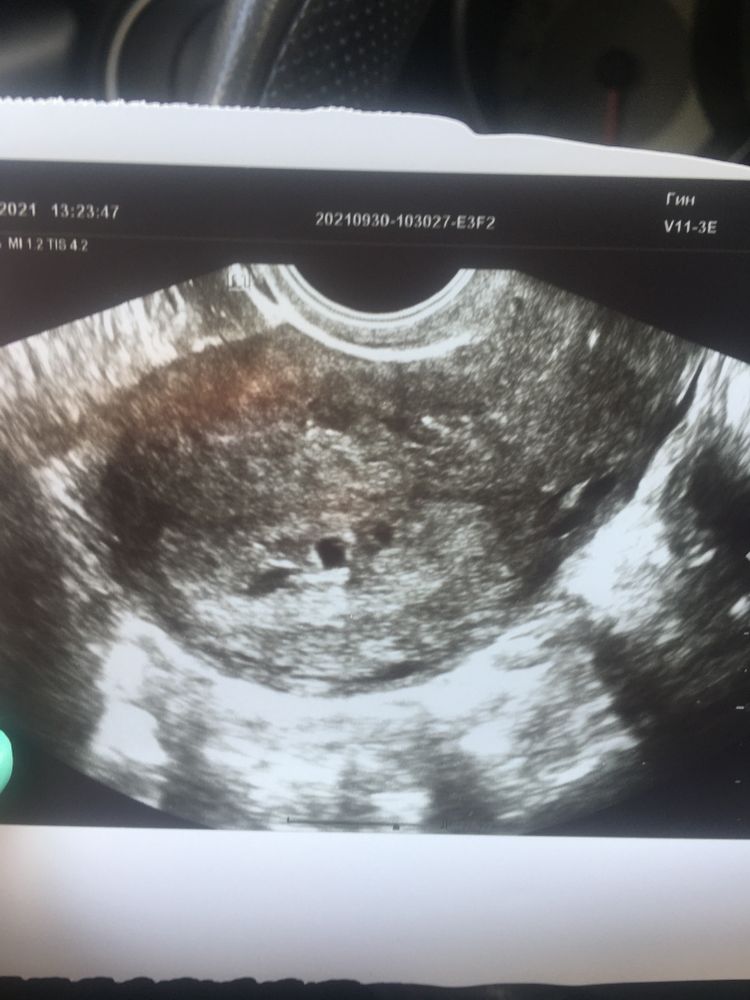

Деформированно плодное яйцо.

Замершая беременность

Девочки,кто видел мои темы сегодня и вчера-я сделала повторное узи. Нашли в полости матки очень маленькое плодное яйцо,всего 4,4 мм. Сказал что оно деформировано,пока конечно рано говорить,но возможна снова замершая😢 Сроку беременности не соответствует,по М сегодня 4 недели и 6 дней в по ПЯ максимум 3. Но,эндометрий хороший,желтое тело хорошее,с хорошим кровотоком,к ПЯ тянутся сосудики,так что ещё очень даже возможно что просто маленький срок,была поздняя овуляция. Так вот хочется надеяться на хорошее. Контроль через неделю,но у меня сегодня должен прийти повторный анализ хгч и после него уже точно будет понятно развивается или нет. Так страшно😞